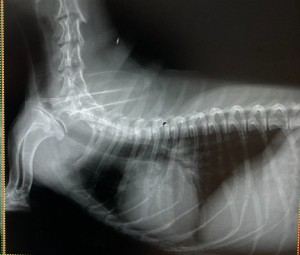

この度レントゲン機器を入れ替え、より鮮明な画像が描出できるようになりました。下の写真は同じワンちゃんのレントゲン写真です。旧機器で撮影したものが1枚目、新機器で撮影したものが2枚目です。

心臓、気管支、胸部の血管、骨の陰影、すべてにおいてより鮮明な画像になっていることが分かります。画質が向上することで診断精度は当然向上します。撮影にかかる時間も大幅に短縮(旧機器で1枚撮影するのに数分かかっていましたが、新機器は数秒)し、動物の負担も格段に減らすことができるようになりました。